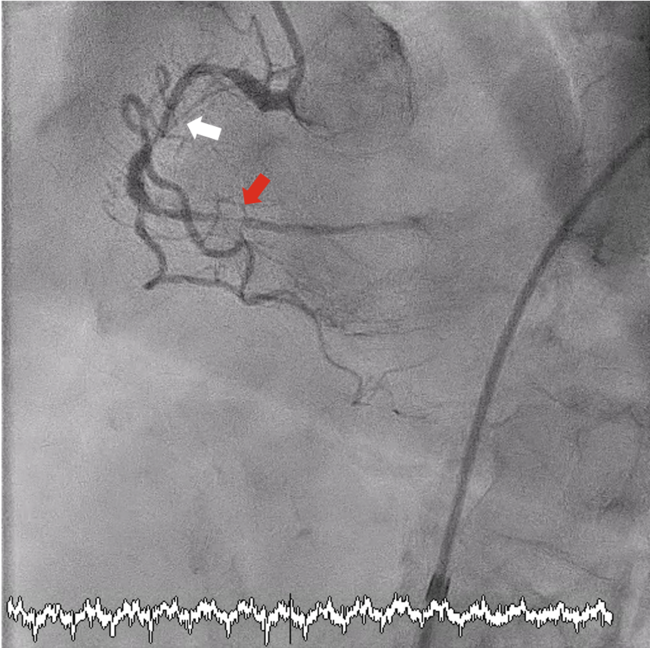

Video 3A. Urgent repeat coronary angiogram revealed distal perforation from a small PDA branch (left anterior oblique view).

Video 3B. Urgent repeat coronary angiogram revealed distal perforation from a small PDA branch (left anterior oblique, cranial view).